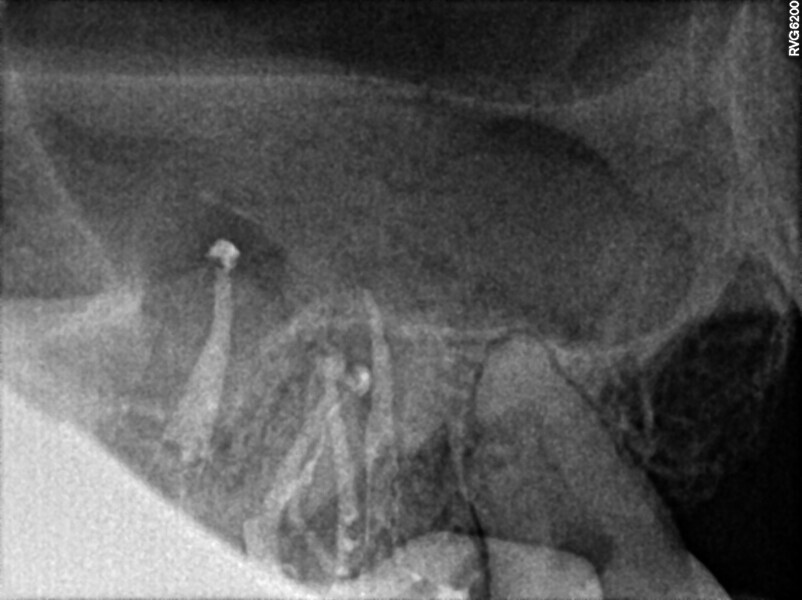

A 25-year-old female patient presented to the office owing to constant pain related to the mandibular left first molar. Pulp necrosis was diagnosed. After the emergency appointment, the patient was referred for complete treatment. The tooth was treated in the same manner as described in the previous paragraphs. After creation of the access cavity, the orifices were located. In the root chamber, the orifices of the MB, mesiolingual, DB, distomesial and distolingual canals were present. After pre-flaring and preparation of the middle third, the LPE enhanced irrigation protocol with the SkyPulse laser was performed. After the irrigation protocol in the mesial root, the irrigants started to flow between lingual and buccal canals. Such an observation suggested to the operator that some space in the isthmus had been created. It is worth mentioning that at this stage apical enlargement was not performed. Final preparation of all five canals was performed with the reciprocating file, and the final irrigation protocol was performed as in the previous case. The radiograph clearly revealed that the isthmus space was filled with the sealer. The radiograph and CBCT image revealed that there were four portals of exit in the mesial root.